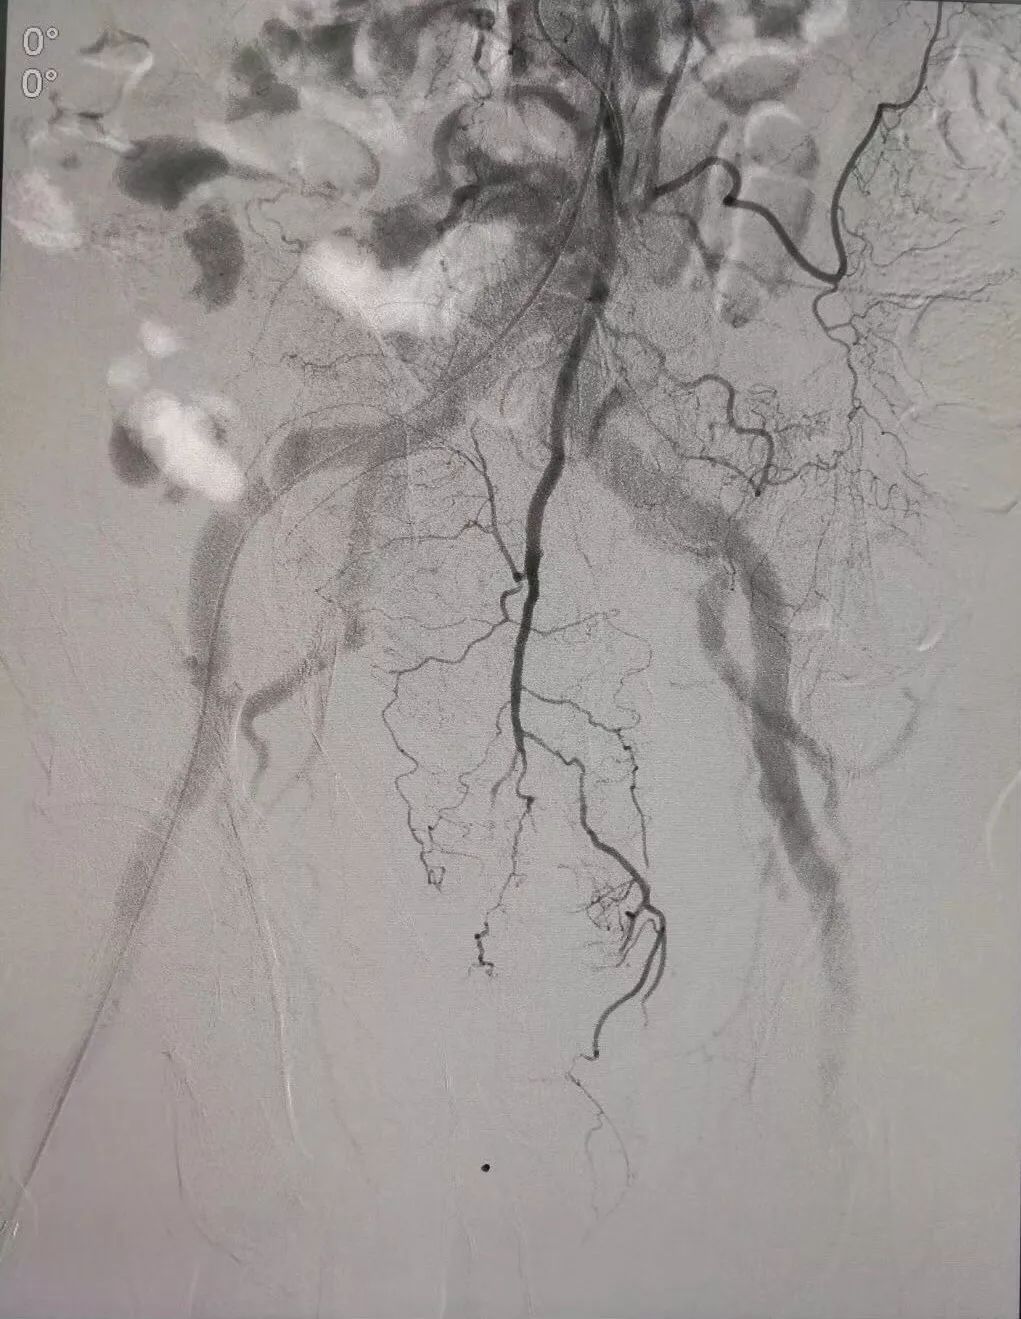

(术前DSA造影提示肠系下动脉增粗、增多、絮乱,临床表现为便血,系破裂出血)